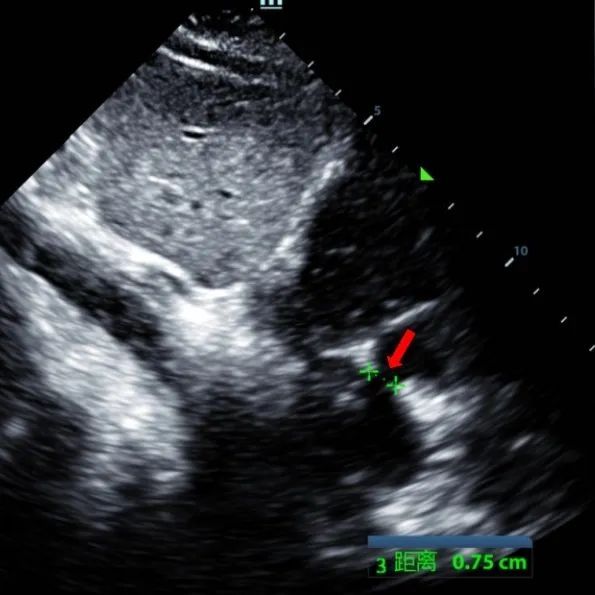

Un maschio di 9 anni con secundum ASD (7,5-7,9mm) è stato trattato utilizzando un sistema di occlusione da 12mm BDASD-I MemoSorb e un sistema di somministrazione 12F. Non sono state rilevate complicazioni o comorbidità prima della procedura.